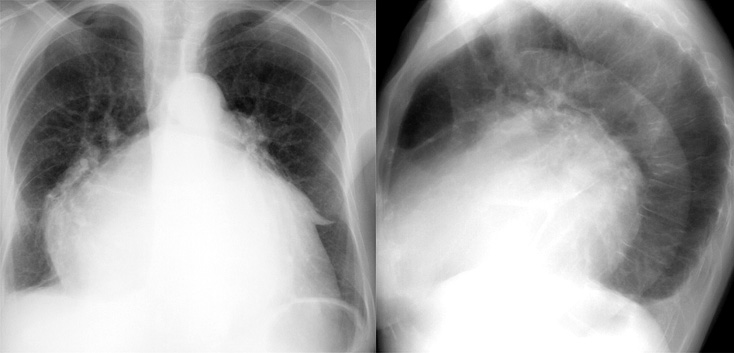

Mitral Valve Disease

Case 11